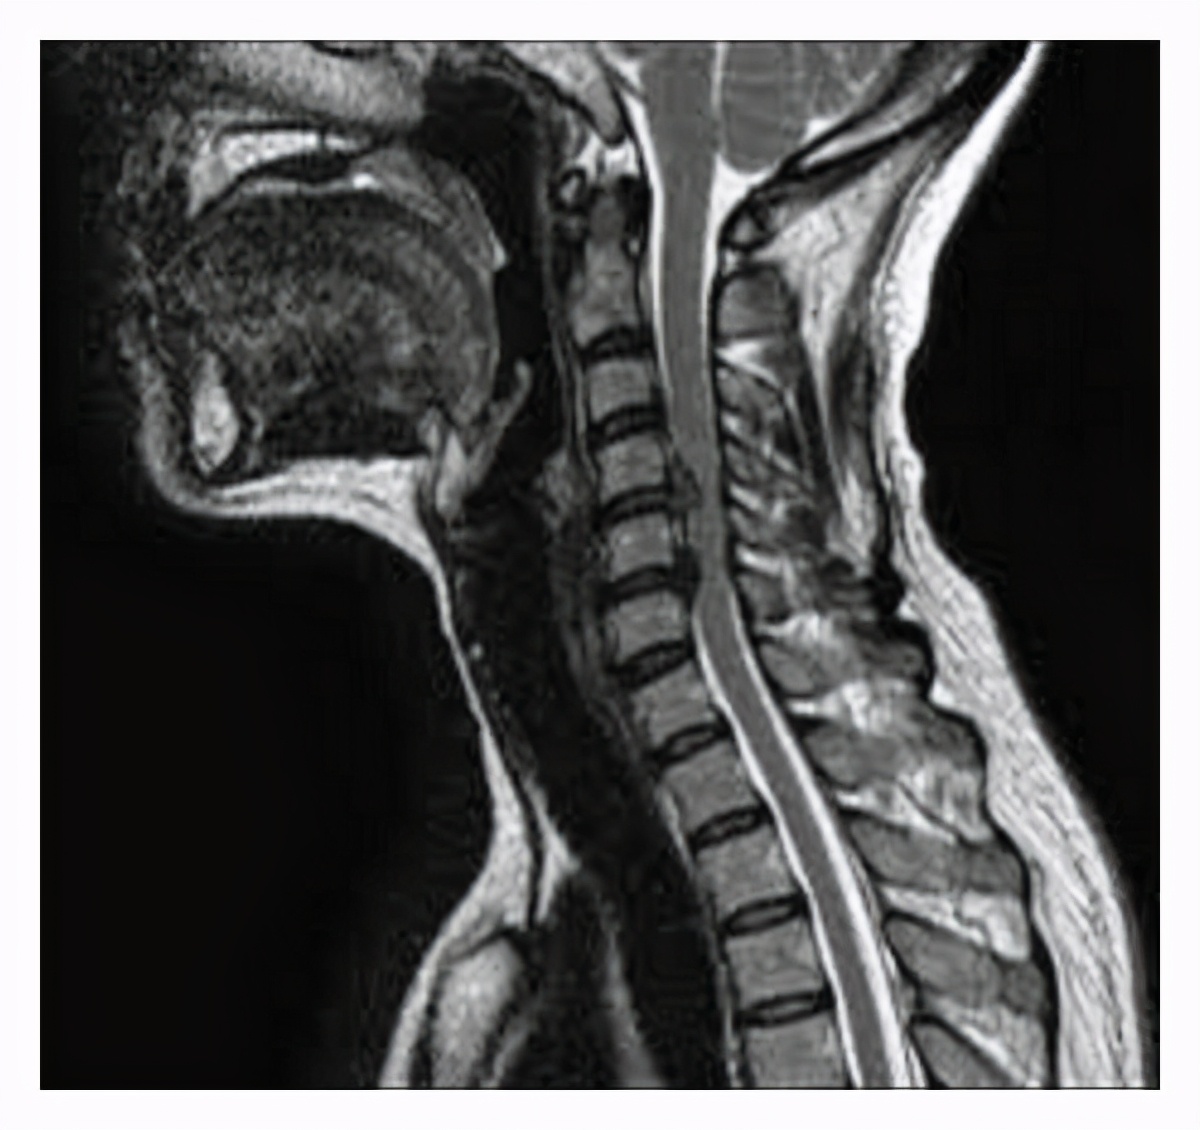

其实颈椎病是有很多类型的,这个患者就是脊髓型颈椎病已经挺严重的了,以前碰到过还跟他说千万不要摔倒,容易瘫痪,没想到冬天天冷路滑真的摔了一跤。

摔跤之后就感觉四肢无力麻木,幸亏送到医院及时做了手术才幸免于瘫痪。

但是最为严重的也是临床中最值得注意的就是脊髓型颈椎病了。

如果脊髓受到压迫,遭受外伤或者其他*力暴**因素之后,就容易出现脊髓损伤,脊髓损伤,大家可能都听过,严重的时候会出现瘫痪。